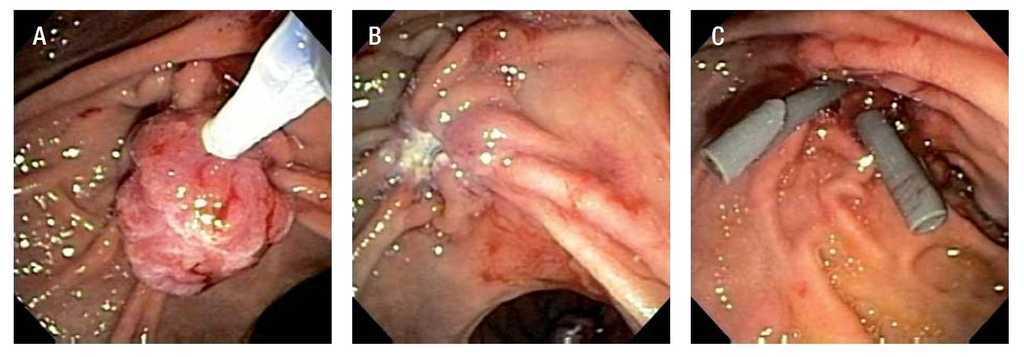

Varón de 63 años de edad con antecedente de esófago de Barrett sin displasia. Durante el estudio endoscópico de seguimiento se identificó una lesión polipoide, ovalada, de alrededor de 20 x 15 mm, sésil y de aspecto digitiforme en la segunda porción del duodeno originada en el ámpula de Vater. Se tomaron múltiples muestras para biopsia de esta lesión (Figura 1). El estudio patológico informó adenoma tubulovelloso negativo para enfermedad maligna. Se realizó ultrasonido endoscópico (Olympus GFUCT140, Aloka alfa 5), que mostró una lesión con ecogenicidad mixta, de predominio hiperecógeno, de cerca de 30 mm, que sólo afectaba mucosa y submucosa (Figura 2). No se observó invasión al colédoco ni el conducto pancreático y tampoco se identificaron adenopatías.

Figura 1. Vista endoscópica de un adenoma del ámpula de Vater.

Se decidió practicar su resección endoscópica con asa de polipectomía (Figura 3A). Previa elevación de la lesión con solución salina y epinefrina con aguja de escleroterapia, se introdujo el asa de polipectomía, con la que se rodeó la lesión por completo; mediante corte y coagulación, la lesión se extirpó en su totalidad sin eventualidades (Figura 3B). Se recuperó el tejido con una red y de inmediato se extendió con agujas en tablillas y se introdujo en formol. Una vez terminada la recuperación de las piezas quirúrgicas se efectuó colangiopancreatografía retrógrada endoscópica y se colocaron dos endoprótesis plásticas, de 10 cm y 10Fr en el conducto biliar y de 4 cm y 7Fr en el conducto pancreático principal (Figura 3C). El informe definitivo de la pieza resecada fue adenoma tubulovelloso, con bordes libres de lesión y sin focos de malignidad. Se siguió en forma estrecha al paciente; las endoprótesis biliar y pancreática se retiraron seis meses después de su colocación. A causa de la asociación de adenomas ampulares con lesiones de igual naturaleza en el colon, el paciente fue sometido a colonoscopia, sin que se encontraran pólipos. A nueve meses del procedimiento, el paciente se encuentra asintomático y en buenas condiciones generales.

Figura 3. A) Resección endoscópica de una lesión en el ámpula de Vater con asa de polipectomía. B) Vista endoscópica después de la resección. C) Endoprótesis biliar (10Fr) y pancreática (7Fr) en posición adecuada.